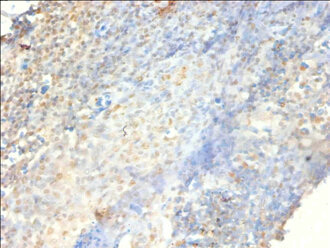

Immunohistochemistry of paraffin-embedded human tonsil tissue using CSB-PA13674A0Rb at dilution of 1:100